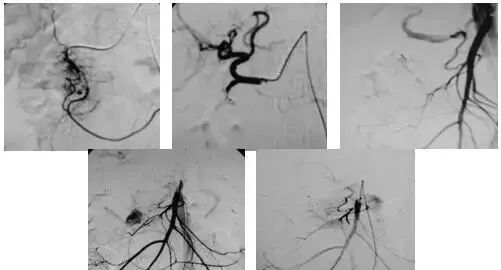

五、出血性疾病:鼻腔大出血、咯血、上消化道大出血、经皮肾镜术后出血、膀胱出血、产后出血等

(5)应用栓塞术或血管加压素治疗胃肠道血管出血。